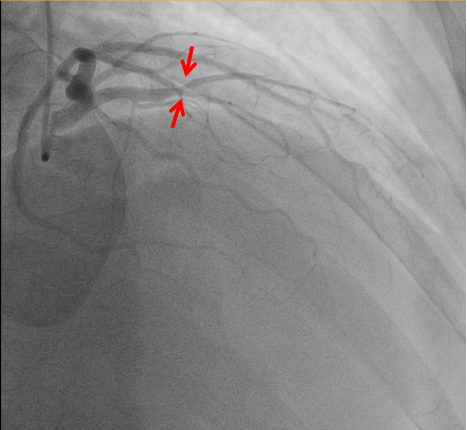

秉持着“时间就是心肌,时间就是生命!”的原则,心血管内科团队迅速到位,在与患者家属进行紧急沟通后,立即为其进行冠状动脉造影检查。造影结果证实了医生的判断——王师傅的心脏重要血管发生了严重狭窄闭塞,其左前降支近中段起完全闭塞。

通过“经皮冠状动脉介入治疗”(PCI),医护人员成功将一枚支架植入堵塞的血管中,恢复了心脏的血液供应。PCI是当前治疗急性心梗最有效的方法之一,能够迅速开通闭塞血管,挽救濒死心肌。